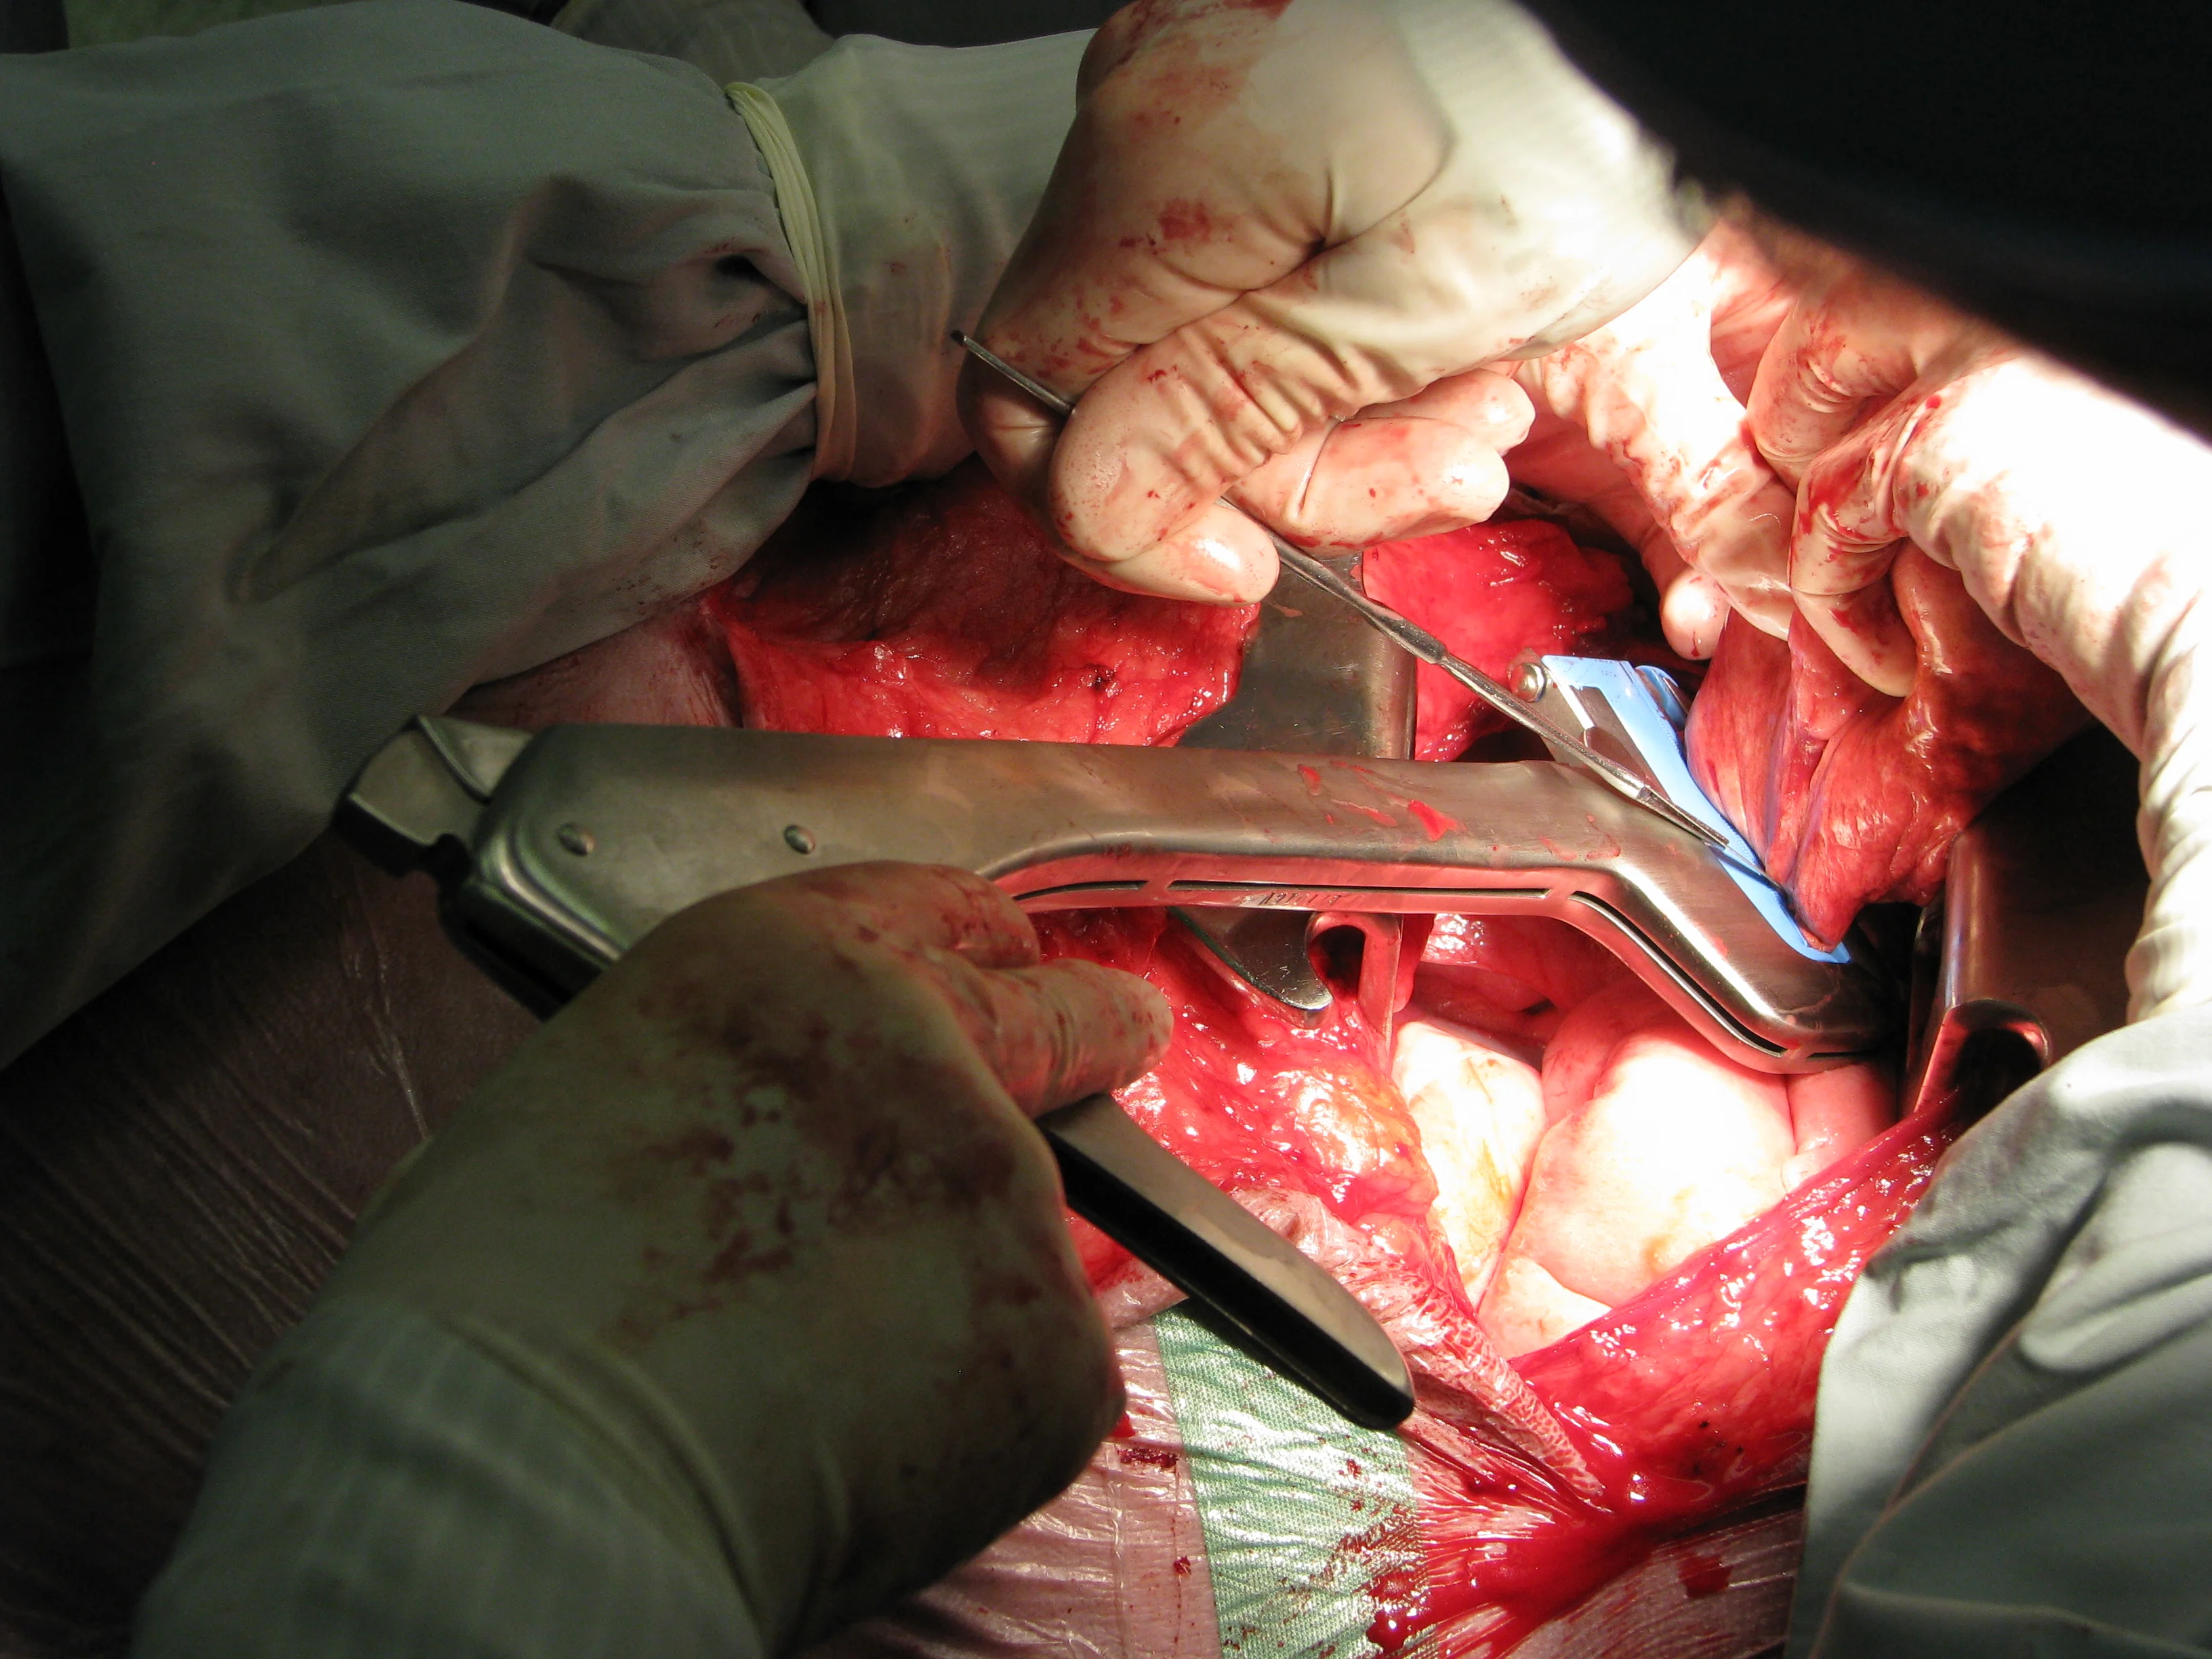

Most solitary lung masses are carcinomas.13 Thoracic CT scan is recommended for staging to assess for lung metastasis and lymphadenomegaly.14 Evidence of either intrapulmonary metastasis or lymph node metastasis can significantly change prognosis with evidence of gross metastatic disease. A lung lobectomy can be performed via a lateral thoracotomy, median sternotomy, or minimally invasive thoracoscopy (Figure 4).

(A) Lateral thoracotomy for removal of a pulmonary bronchogenic carcinoma (located between the thumb and index finger of the surgeon’s right hand). (B) Resection of the mass with the aid of a thoracoabdominal stapling device